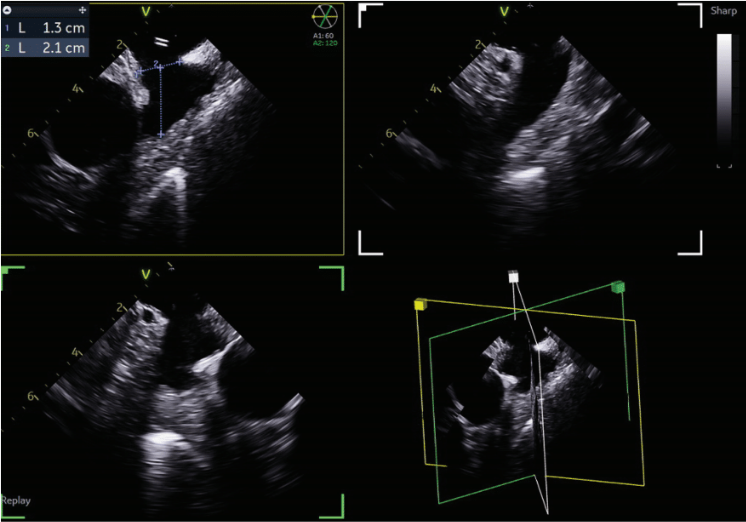

quickly adopted for most cases. The typical workflow for incorporating the 4D ICE catheter involves femoral venous access in the usual manner. To begin a case, the catheter is inserted into the right atrium (RA) and screened for pericardial effusion. Using the V-Plane feature, the LV pericardium can be visualized as well. The catheter is then deflected across the tricuspid valve and into the right ventricular outflow tract. V-Plane through the appendage, in addition to standard 2D imaging, can exclude LAA thrombus (Figure 1). The catheter is withdrawn back to the RA and imaging of the interatrial septum is obtained to help guide transseptal puncture in the usual manner. Once puncture is completed, the septum is flossed with the transseptal sheath. The sheath is then pulled back to the inferior vena cava (IVC). The ICE catheter is then withdrawn to the low RA with direct visualization of the wire as it crosses the septum. Under ultrasound and fluoroscopic guidance, the ICE catheter is pushed across the septum into the mid LA. The delivery sheath is then pushed across the puncture site into the LA. The ICE catheter can be positioned in different locations throughout the LA; however, placement along the mitral annulus frequently allows adequate visualization of the LAA (Figure 2). Multiplanar imaging of the LAA allows for device sizing and selection (Figure 3). Once a device size is selected, the implant is prepped and delivered using multiplanar and fluoroscopic imaging. During sheath manipulation and device delivery, the sonographer can make fine adjustments to the image to maintain adequate visualization so the operator can focus on device delivery. Once an implant is delivered, confirmation of position and occlusion can easily be performed by color flow Doppler and 2D/3D imaging (Figure 4). At the end of the procedure, a quick survey can exclude pericardial effusion.